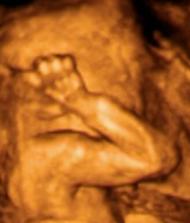

Ultrazvuky a bruska

krasne 4D fotky 🙂